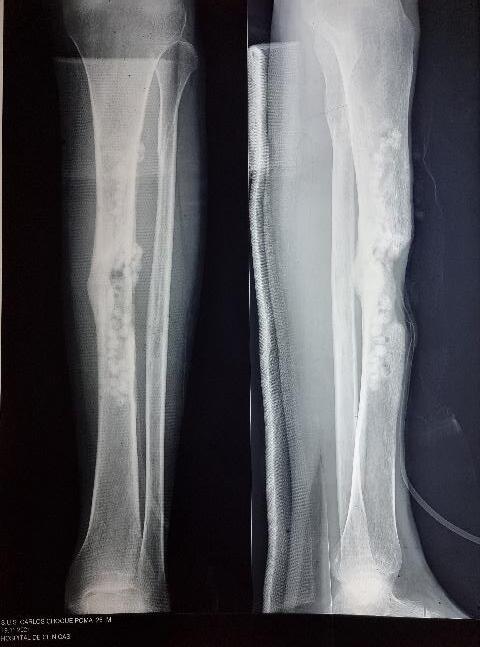

Uso de terapia de cierre asistido por vacío artesanal para el tratamiento de defecto de partes blandas en paciente postoperado de osteomielitis crónica en tibia

Use of artisanal vacuum-assisted closure therapy for the reatment of soft tissue defects in a postoperative patient with chronic tibial osteomyelitis

Eduardo Monasterios, Alvaro Mamani, Cristian Mostacedo